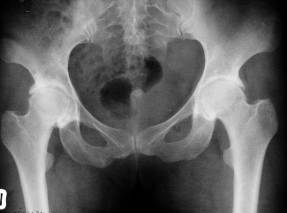

LUXAŢIA CONGENITALA A sOLDULUI apare în cursul vietii intrauterine sau în primele luni de viata, mai ales la fetitele nascute în prezentatie pelviana.

La copilul care nu a umblat

Femurul de partea luxata este mai subtire si mai osteoporotic;

Diafiza femurala este departata de oasele bazinului

În luxatia unilaterala este o asimetrie între cele doua extremitati superioare

Cavitatea cotiloida este aplatizata (aspect de farfurie întinsa)

Unghiul de înclinatie al acetabulului este sub 30°. În luxatia congenitala de sold acest unghi este marit.

La copilul care a umblat în afara de semnele radiologice descrise, se mai constata urmatoarele:

Nucleul osos al capului femural apare mai târziu, chiar la doi ani (în mod normal la 8-10 luni);

Nucleul epifizar de partea luxata este mai mic decât în partea sanatoasa;

Cavitatea cotiloida de partea luxata are forma unei farfurii întinse, este alungita si foarte putin adânca;

Arcul cervico-obturator este întrerupt de partea luxata.

În mod normal, osificarea ramurilor ischiopubiene se face la 5 - 6 ani; în caz de luxatie se produce tardiv dupa vârsta de 7-8 ani.